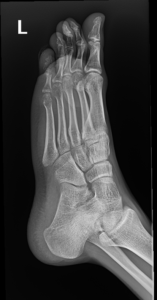

- Foot Fractures.